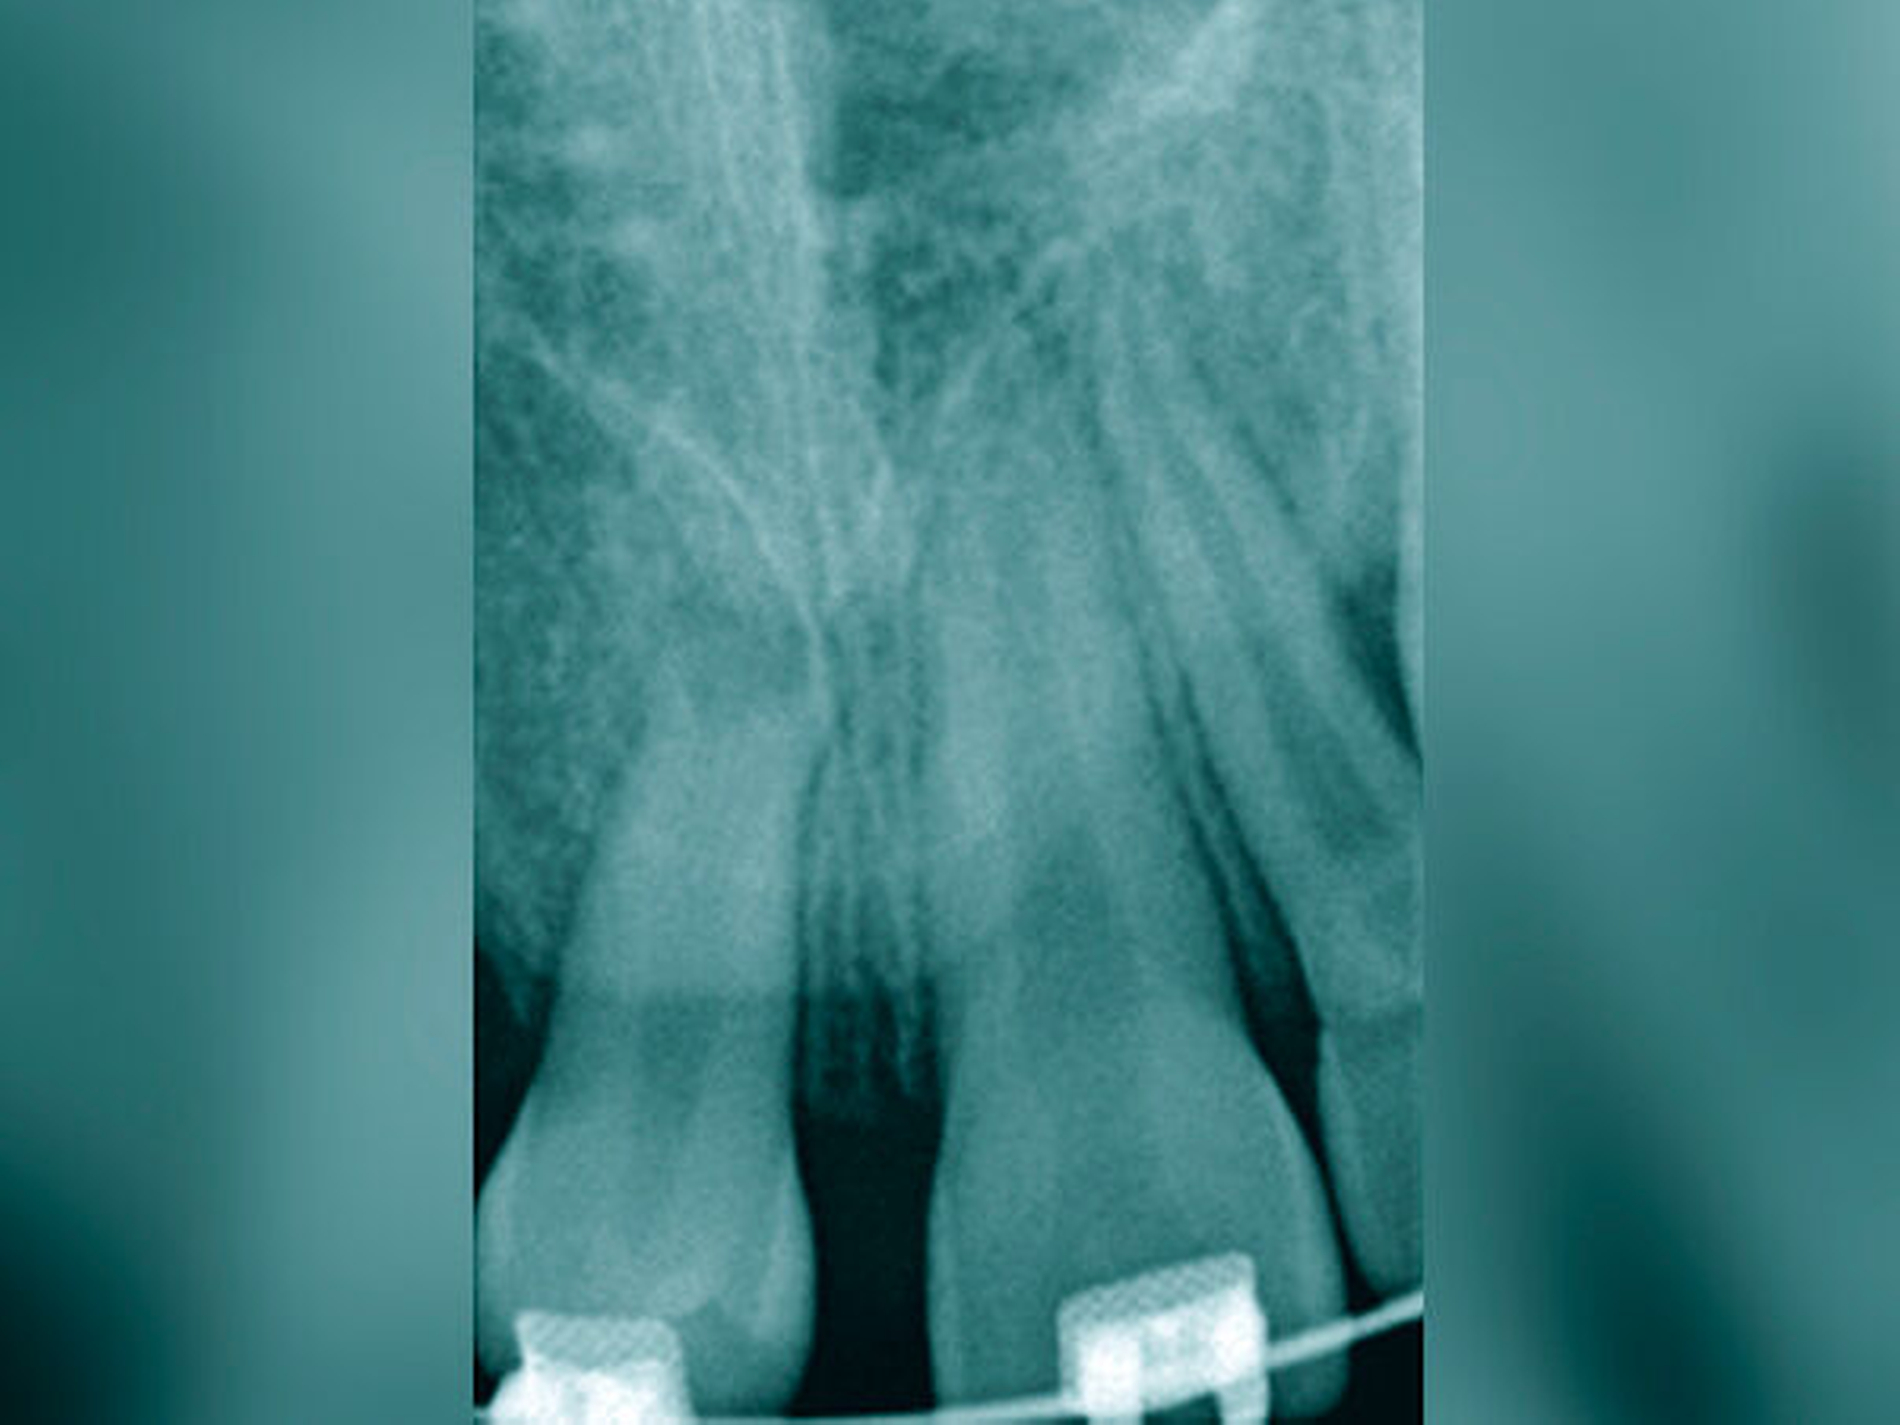

In beiden Falldarstellungen wurden diese Bedingungen eingehalten. Eine Besonderheit stellt die Kombination von kieferorthopädischem Lückenschluss und Autotransplantation im zweiten Fall dar. Hier war vor der Rekonstruktion mittels Kompositaufbau eine Bewegung des Transplantats und der rechten Seitenzahnreihe erforderlich. Beides gestaltete sich ohne Probleme und sollte auch beim Verlust mehrerer Schneidezähne bedacht werden. Der Lückenschluss im Unterkiefer nach Keimentnahme konnte mithilfe skelettaler Verankerung ebenfalls reibungslos erfolgen. Es sollte jedoch wie beim kieferorthopädischen Lückenschluss die Anlage der dritten Molaren in der verkürzten Zahnreihe geprüft werden, um für den zweiten Molaren des Gegenkiefers einen Antagonisten zu haben. Ziel des Beitrags war es, die Autotransplantation nach Frontzahnverlust und Aplasie ins differenzialdiagnostische und -therapeutische Spektrum als gleichberechtigte Variante einzubeziehen.

Die große Regenerationspotenz des Zahnkeims, insbesondere während des Wurzelwachstums, ist Garant für deren Fortsetzung und den Erhalt der Vitalität in einer neu präparierten Alveole. Andreasen et al. [2007] bezeichnen die Neuformierung des Parodonts als den Schlüssel für eine erfolgreiche Transplantation. Zwei Drittel des Wurzelwachstums, ein offenes Foramen apicale (> 2 mm) und ein einwurzeliger Prämolar aus dem Unterkiefer gibt er als ideale Voraussetzungen für eine Erfolgsrate von 100 Prozent an. Eine weitere Voraussetzung ist die rasche Transplantation von der Spender- in die Empfängeralveole. Die Präparation der Schneidezahnalveole mit einem Dummy garantiert die optimale Passfähigkeit.